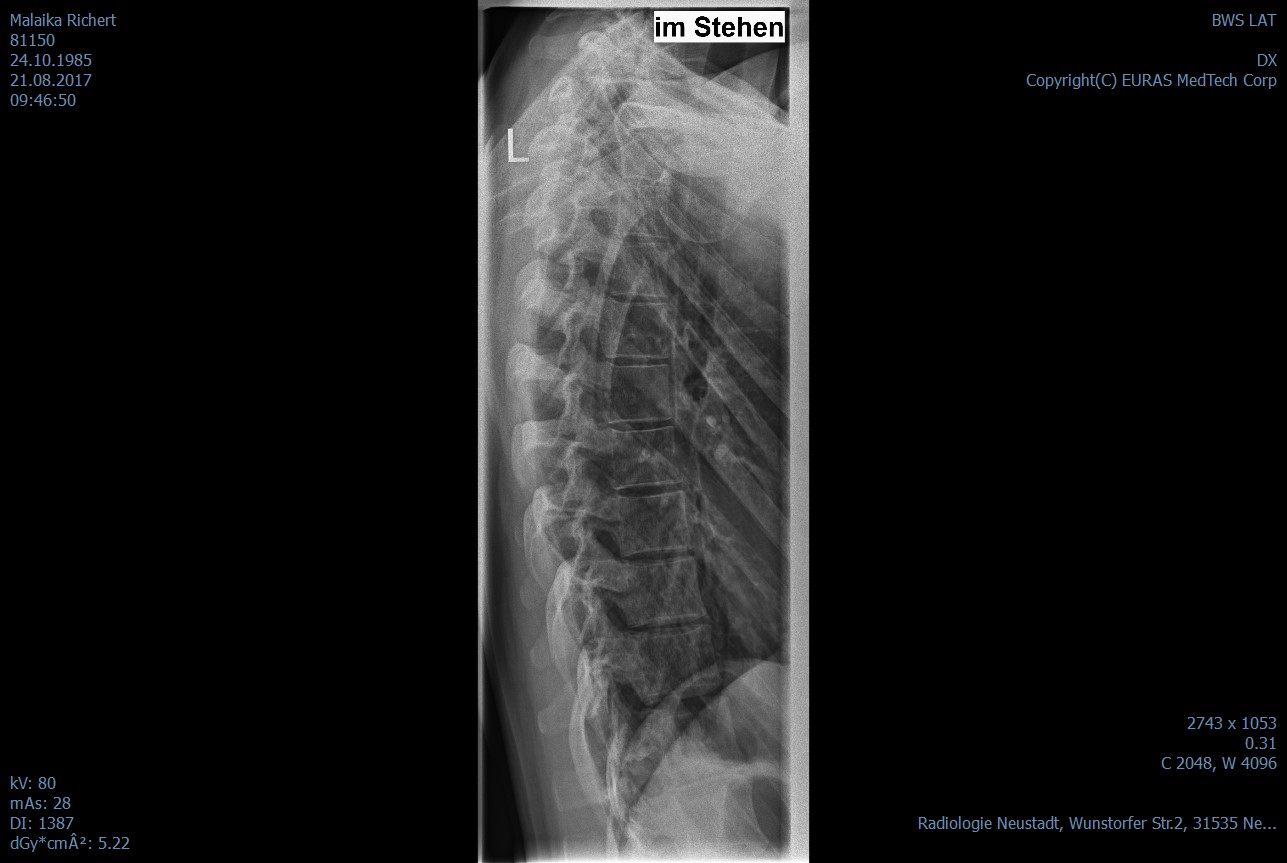

Ich hoffe ich habe alles erwähnt. Was soll ich tun? was meint und empfehlt ihr mir? Ich habe die Röntgenbilder mit eingefügt.

Zuerstmal bin ich irritiert, weil ich nicht verstehe, wie ein Arzt bei der Wirbelsäule von einer Skoliose sprechen kann. Von einer Skoliose spricht man erst ab 20°, und das sind vielleicht gerade mal 5°, so wie ich das schätze. Ich bin, wie gesagt, kein Fachmann, und ich konnte nur eine der beiden Dateien öffnen, aber das scheint mir falscher Alarm zu sein.

Es schaut wohl so aus. Das die Skoliose wirklich sehr sehr gering ist und nichts mit meinem Schmerz zu tun habe.